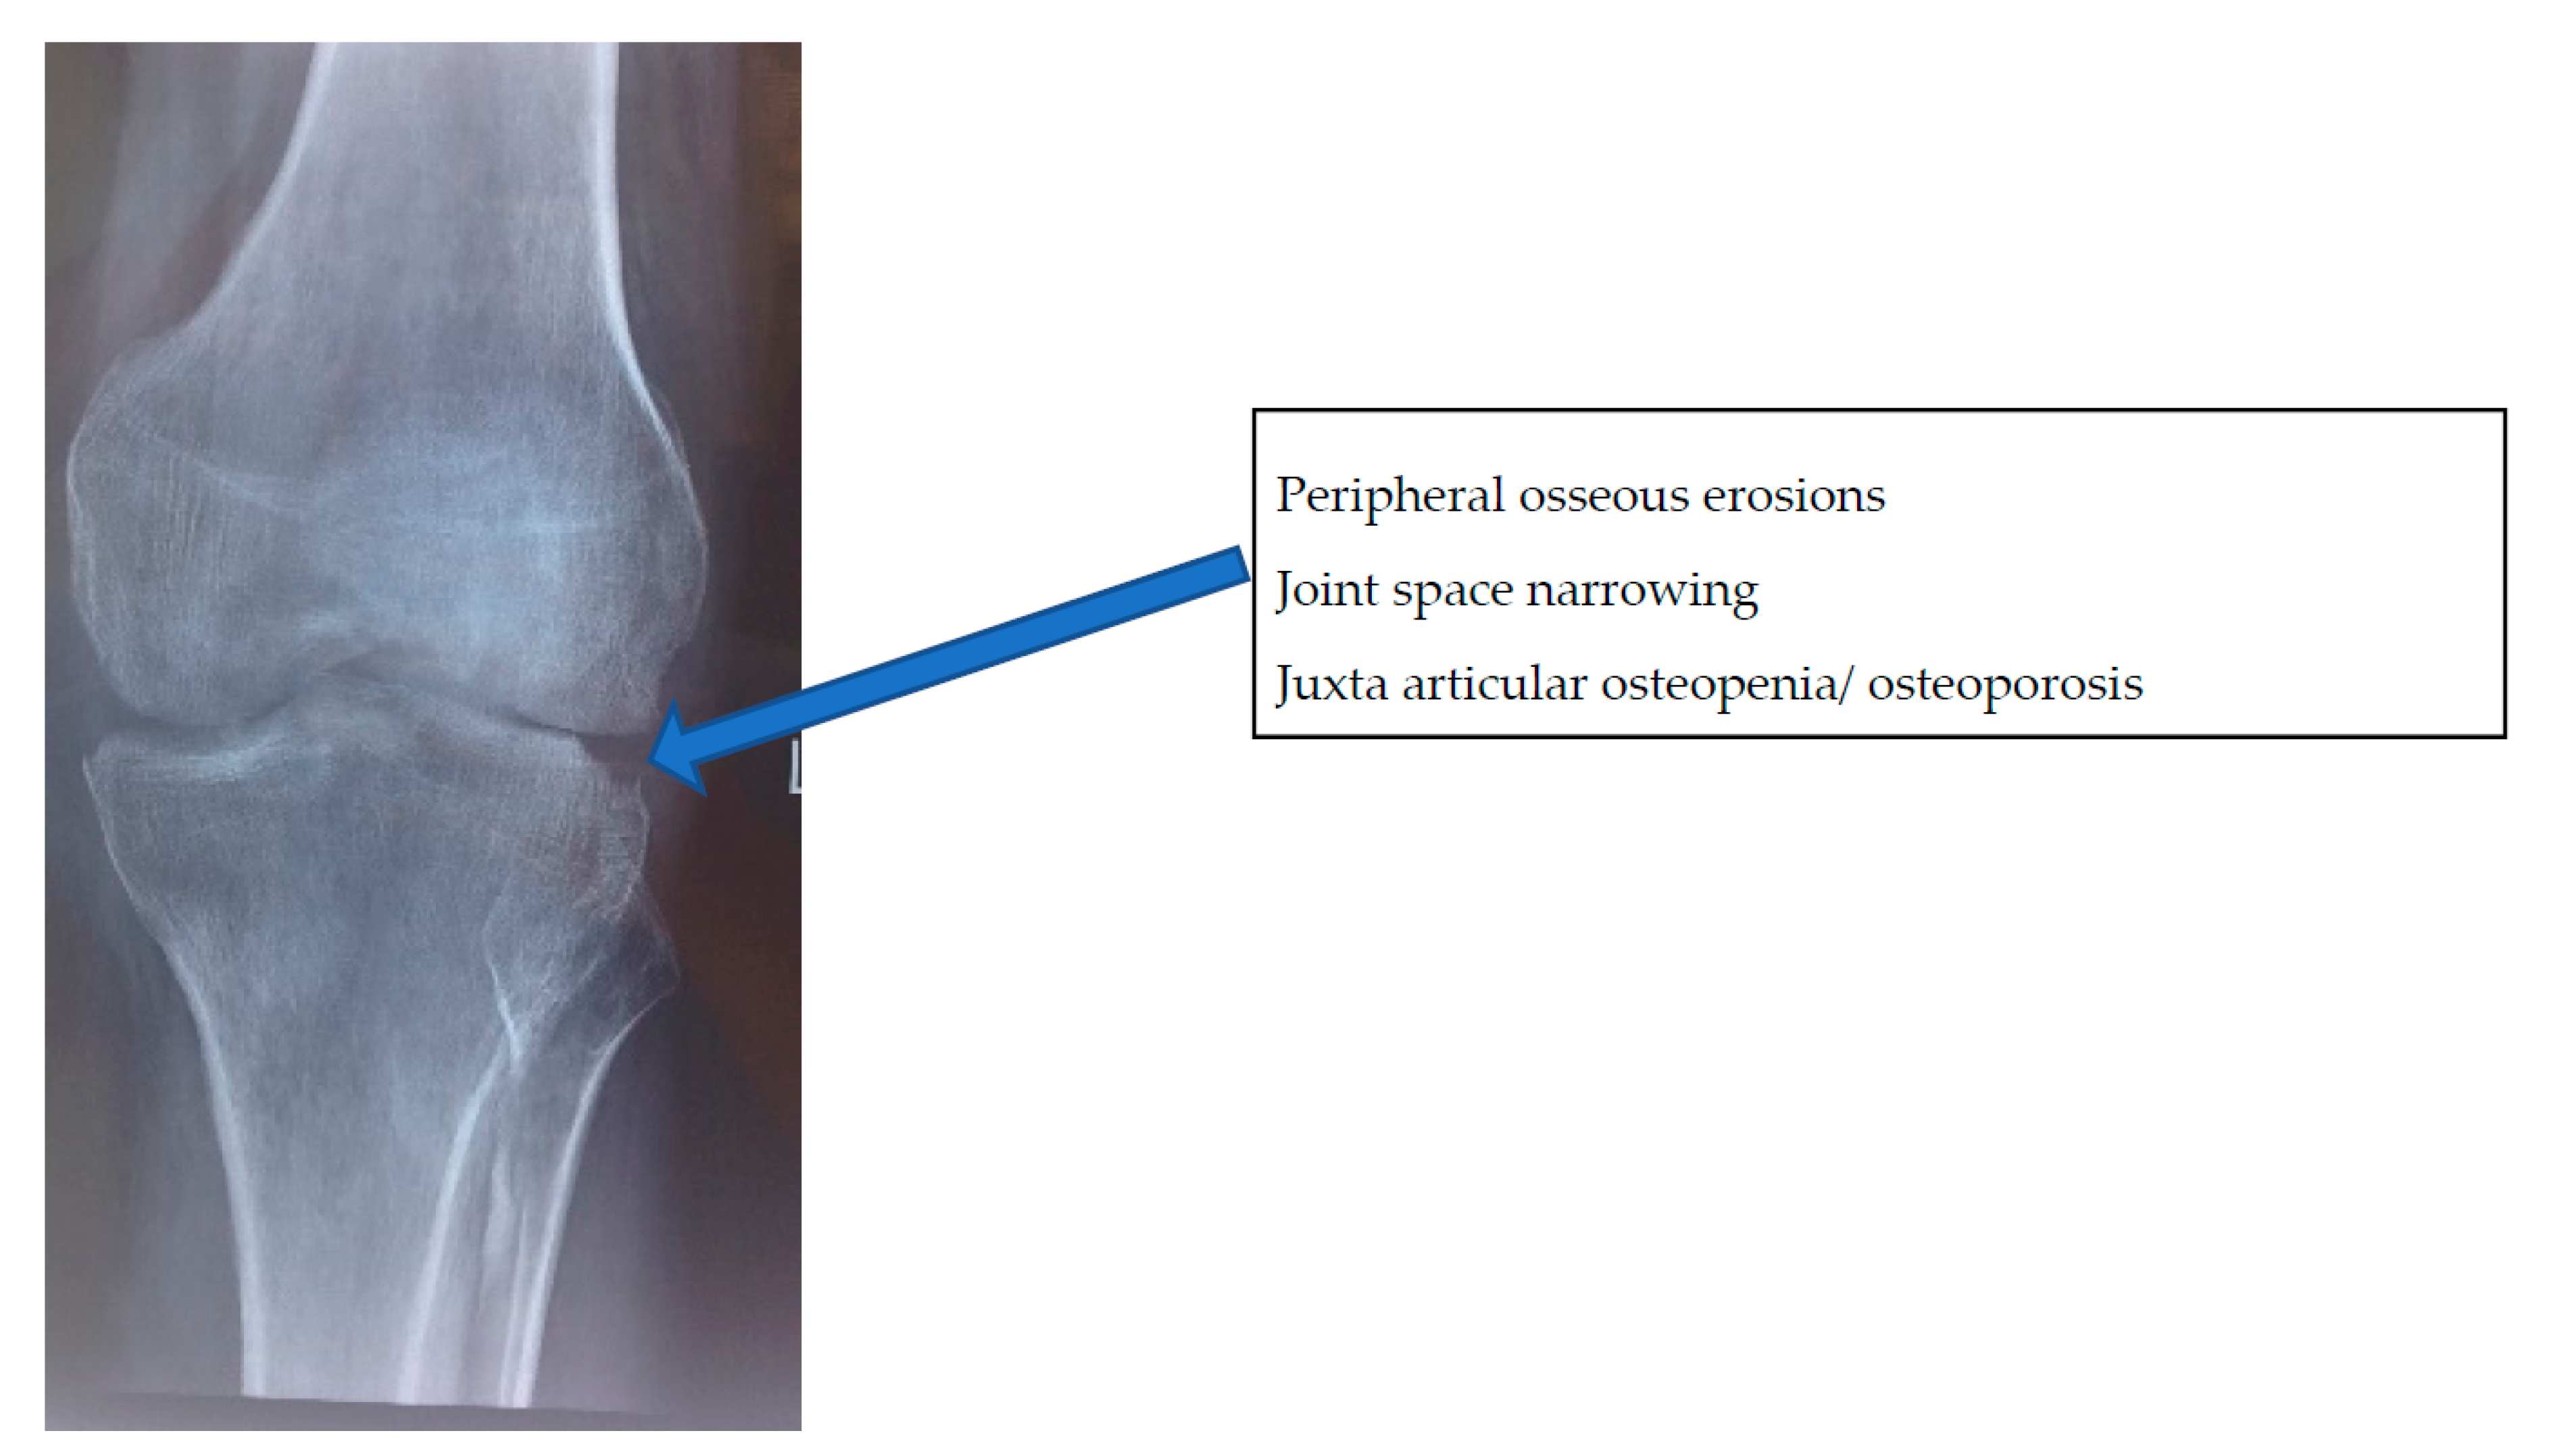

- Stage of early arthritis. Patient presents with joint pain, spasm of the surrounding muscle, and difficulty in doing some activities of daily living. Affected joint has 50–75% of the joint movement preserved. X-ray shows classical Phemister’s triad of juxta-articular osteopenia, mild joint space reduction, and peripheral osseous erosions. This stage has good prognosis with mild stiffness.